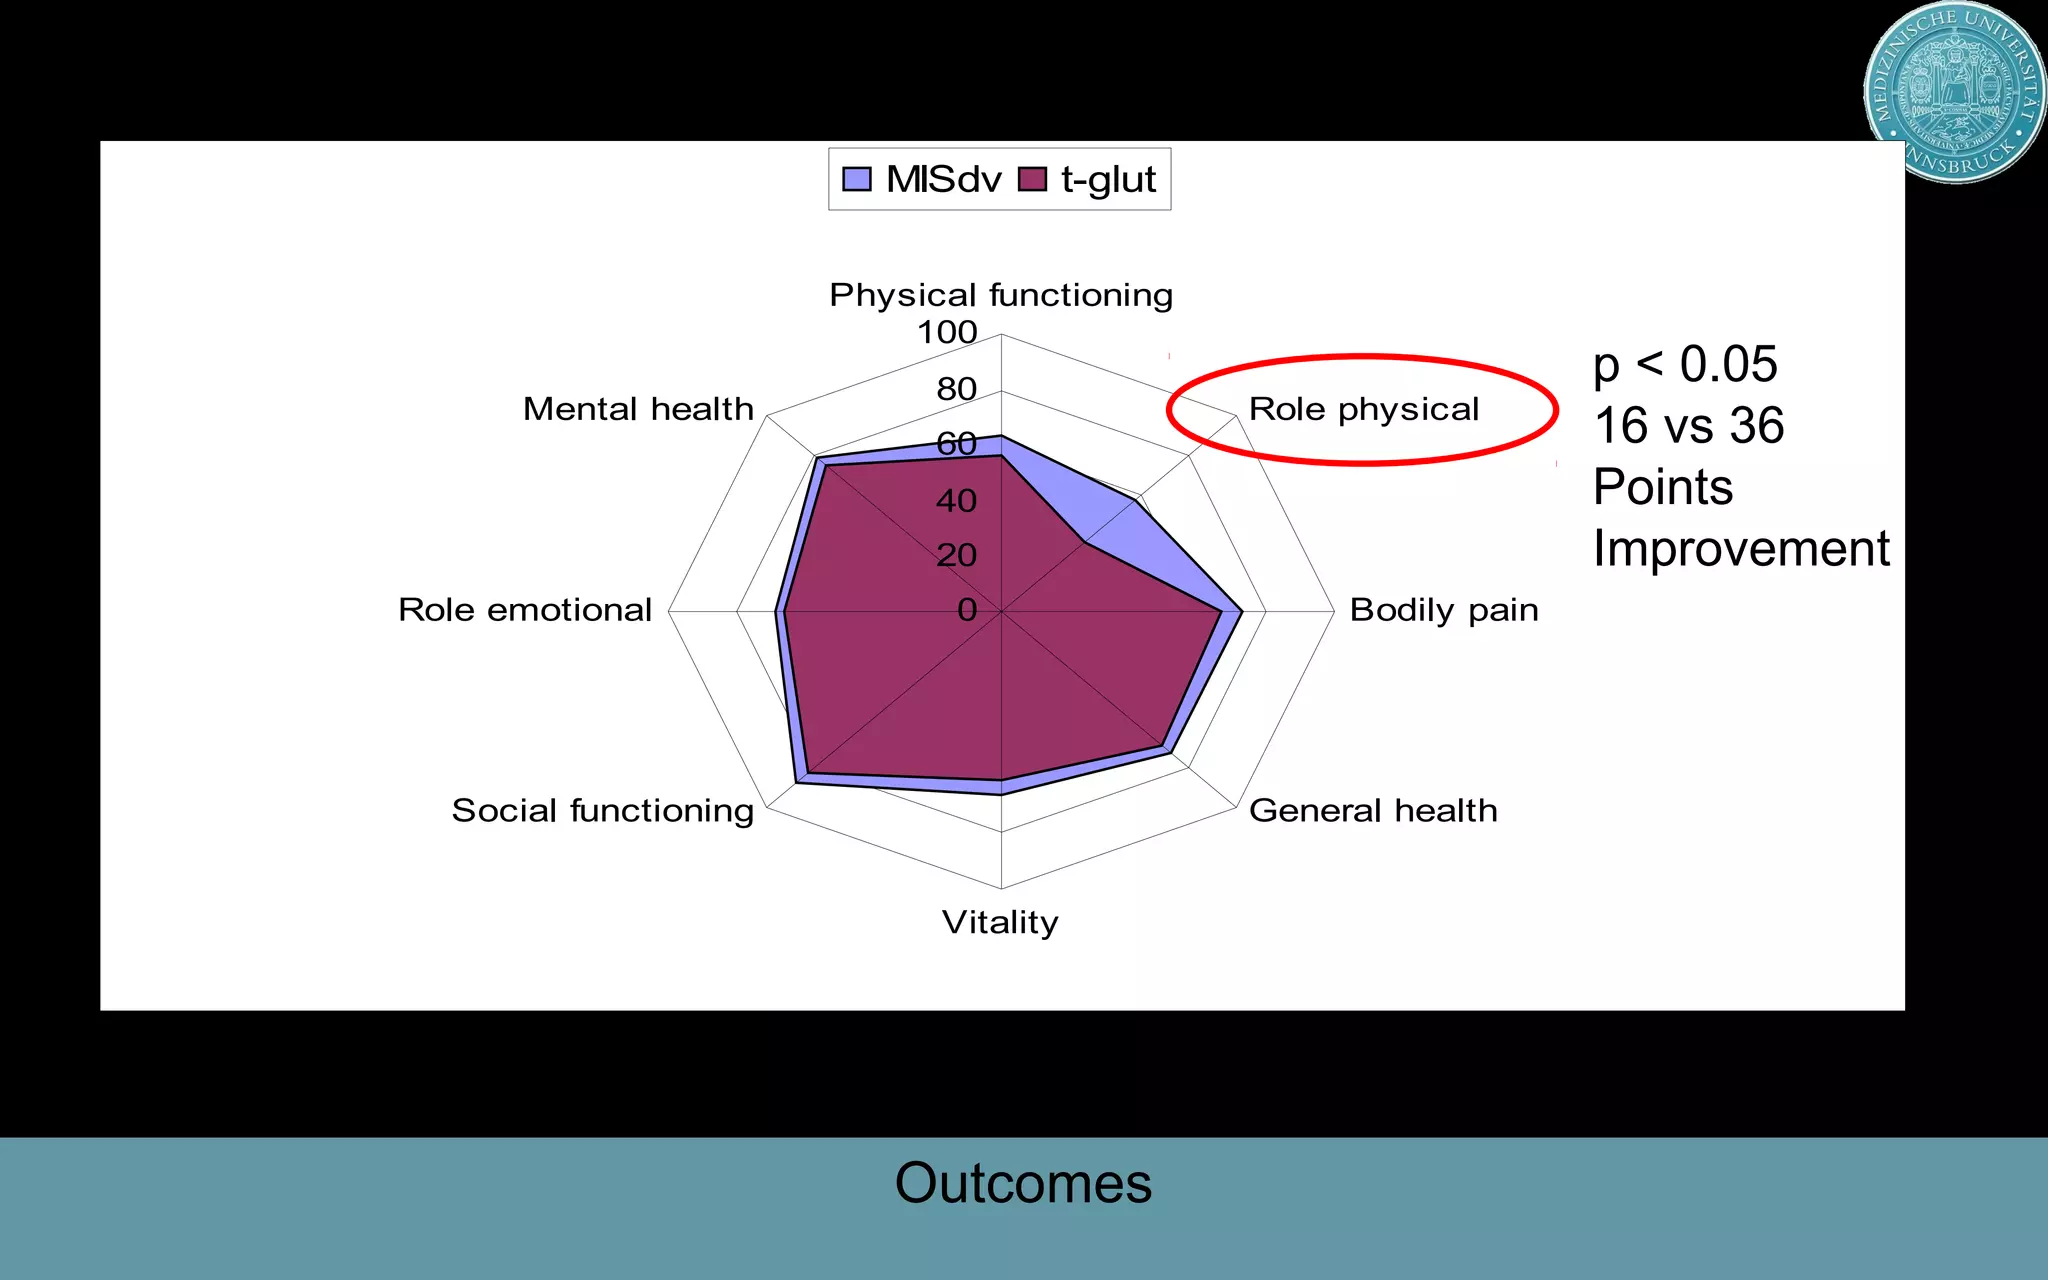

This document discusses the direct anterior approach for total hip arthroplasty. It lists advantages of the direct anterior approach such as increased stability, easier leg length equalization, lower costs by not requiring an operating table, reduced radiation exposure, faster rehabilitation, and lower risk of deep vein thrombosis. The document also discusses the historical background of the direct anterior approach, showing it has been performed since the 1880s. It presents images showing fatty degeneration of muscles and gluteal atrophy after total hip arthroplasty. Finally, it displays graphs comparing outcomes and improvements in quality of life domains between the direct anterior approach and minimally invasive approaches.